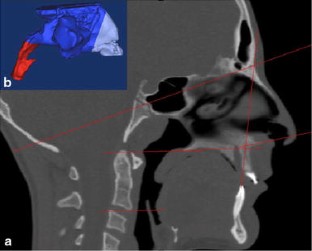

Fig. 2